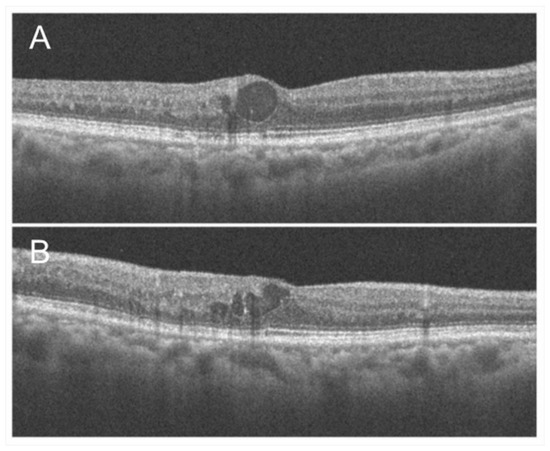

3.3. Macular Edema

- Hasegawa, T.; Ueda, T.; Okamoto, M.; Ogata, N. Presence of foveal bulge in optical coherence tomographic images in eyes with macular edema associated with branch retinal vein occlusion. Am. J. Ophthalmol. 2014, 157, 390–396.e1. [Google Scholar] [CrossRef]

- Hasegawa, T.; Masuda, N.; Ogata, N. Highly reflective line in optical coherence tomography images of eyes with macular edema associated with branch retinal vein occlusion. Am. J. Ophthalmol. 2015, 159, 925–933.e1. [Google Scholar] [CrossRef]

- Mimouni, M.; Segev, O.; Dori, D.; Geffen, N.; Flores, V.; Segal, O. Disorganization of the Retinal Layers as a Predictor of visual acuity in eyes with macular edema secondary to vein occlusion. Am. J. Ophthalmol. 2017, 182, 160–167. [Google Scholar] [CrossRef]